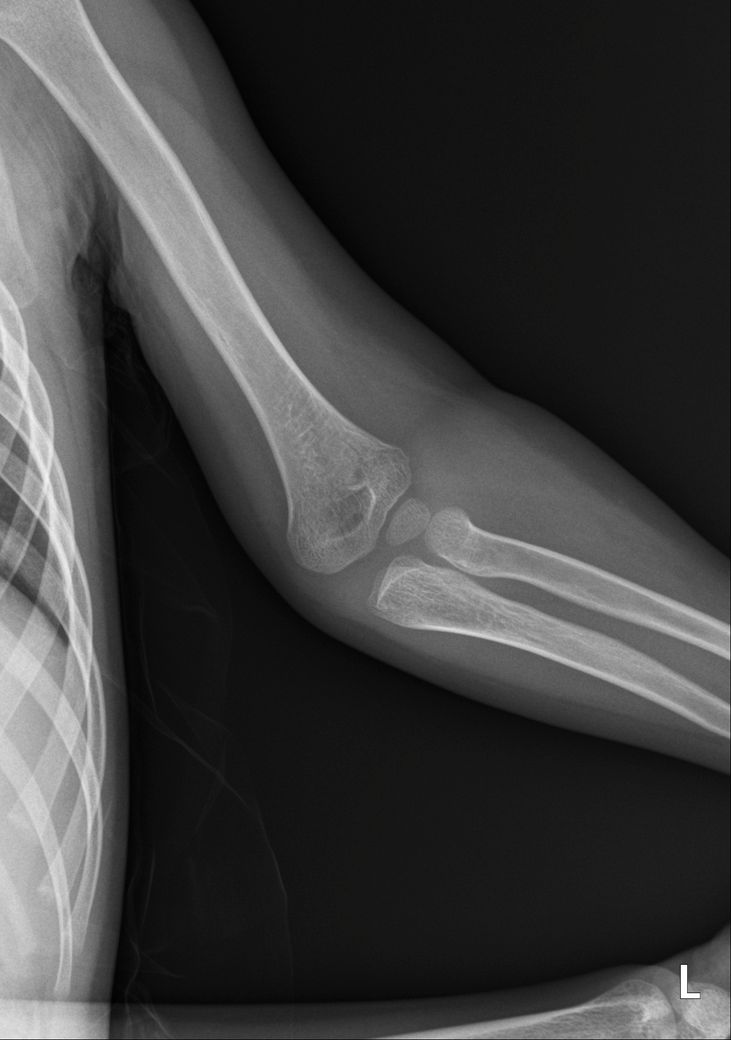

소아팔꿈치골절 씨티나 엠알아이 찍어 봐야할까요?

안녕하세요 엑스레이상 골절 확인되었는데 사고시 팔이 꺾여 아빠가 팔을 돌렸다고 해요 성장판 인대 근육도 걱정이 되는데 씨티나 엠알아이 검사를 추가로 해야할까요?

병원에서는 씨티는 권유하시는데 방사능이 걱정되어 고민중입니다 일요일 다쳤고 월요일 병원 진료 후 통깁스중입니다 성장판 쪽은 아니라고 하시던데 성장판 괜찮을까요?

• 1번 째 사진

• 3번 째 사진